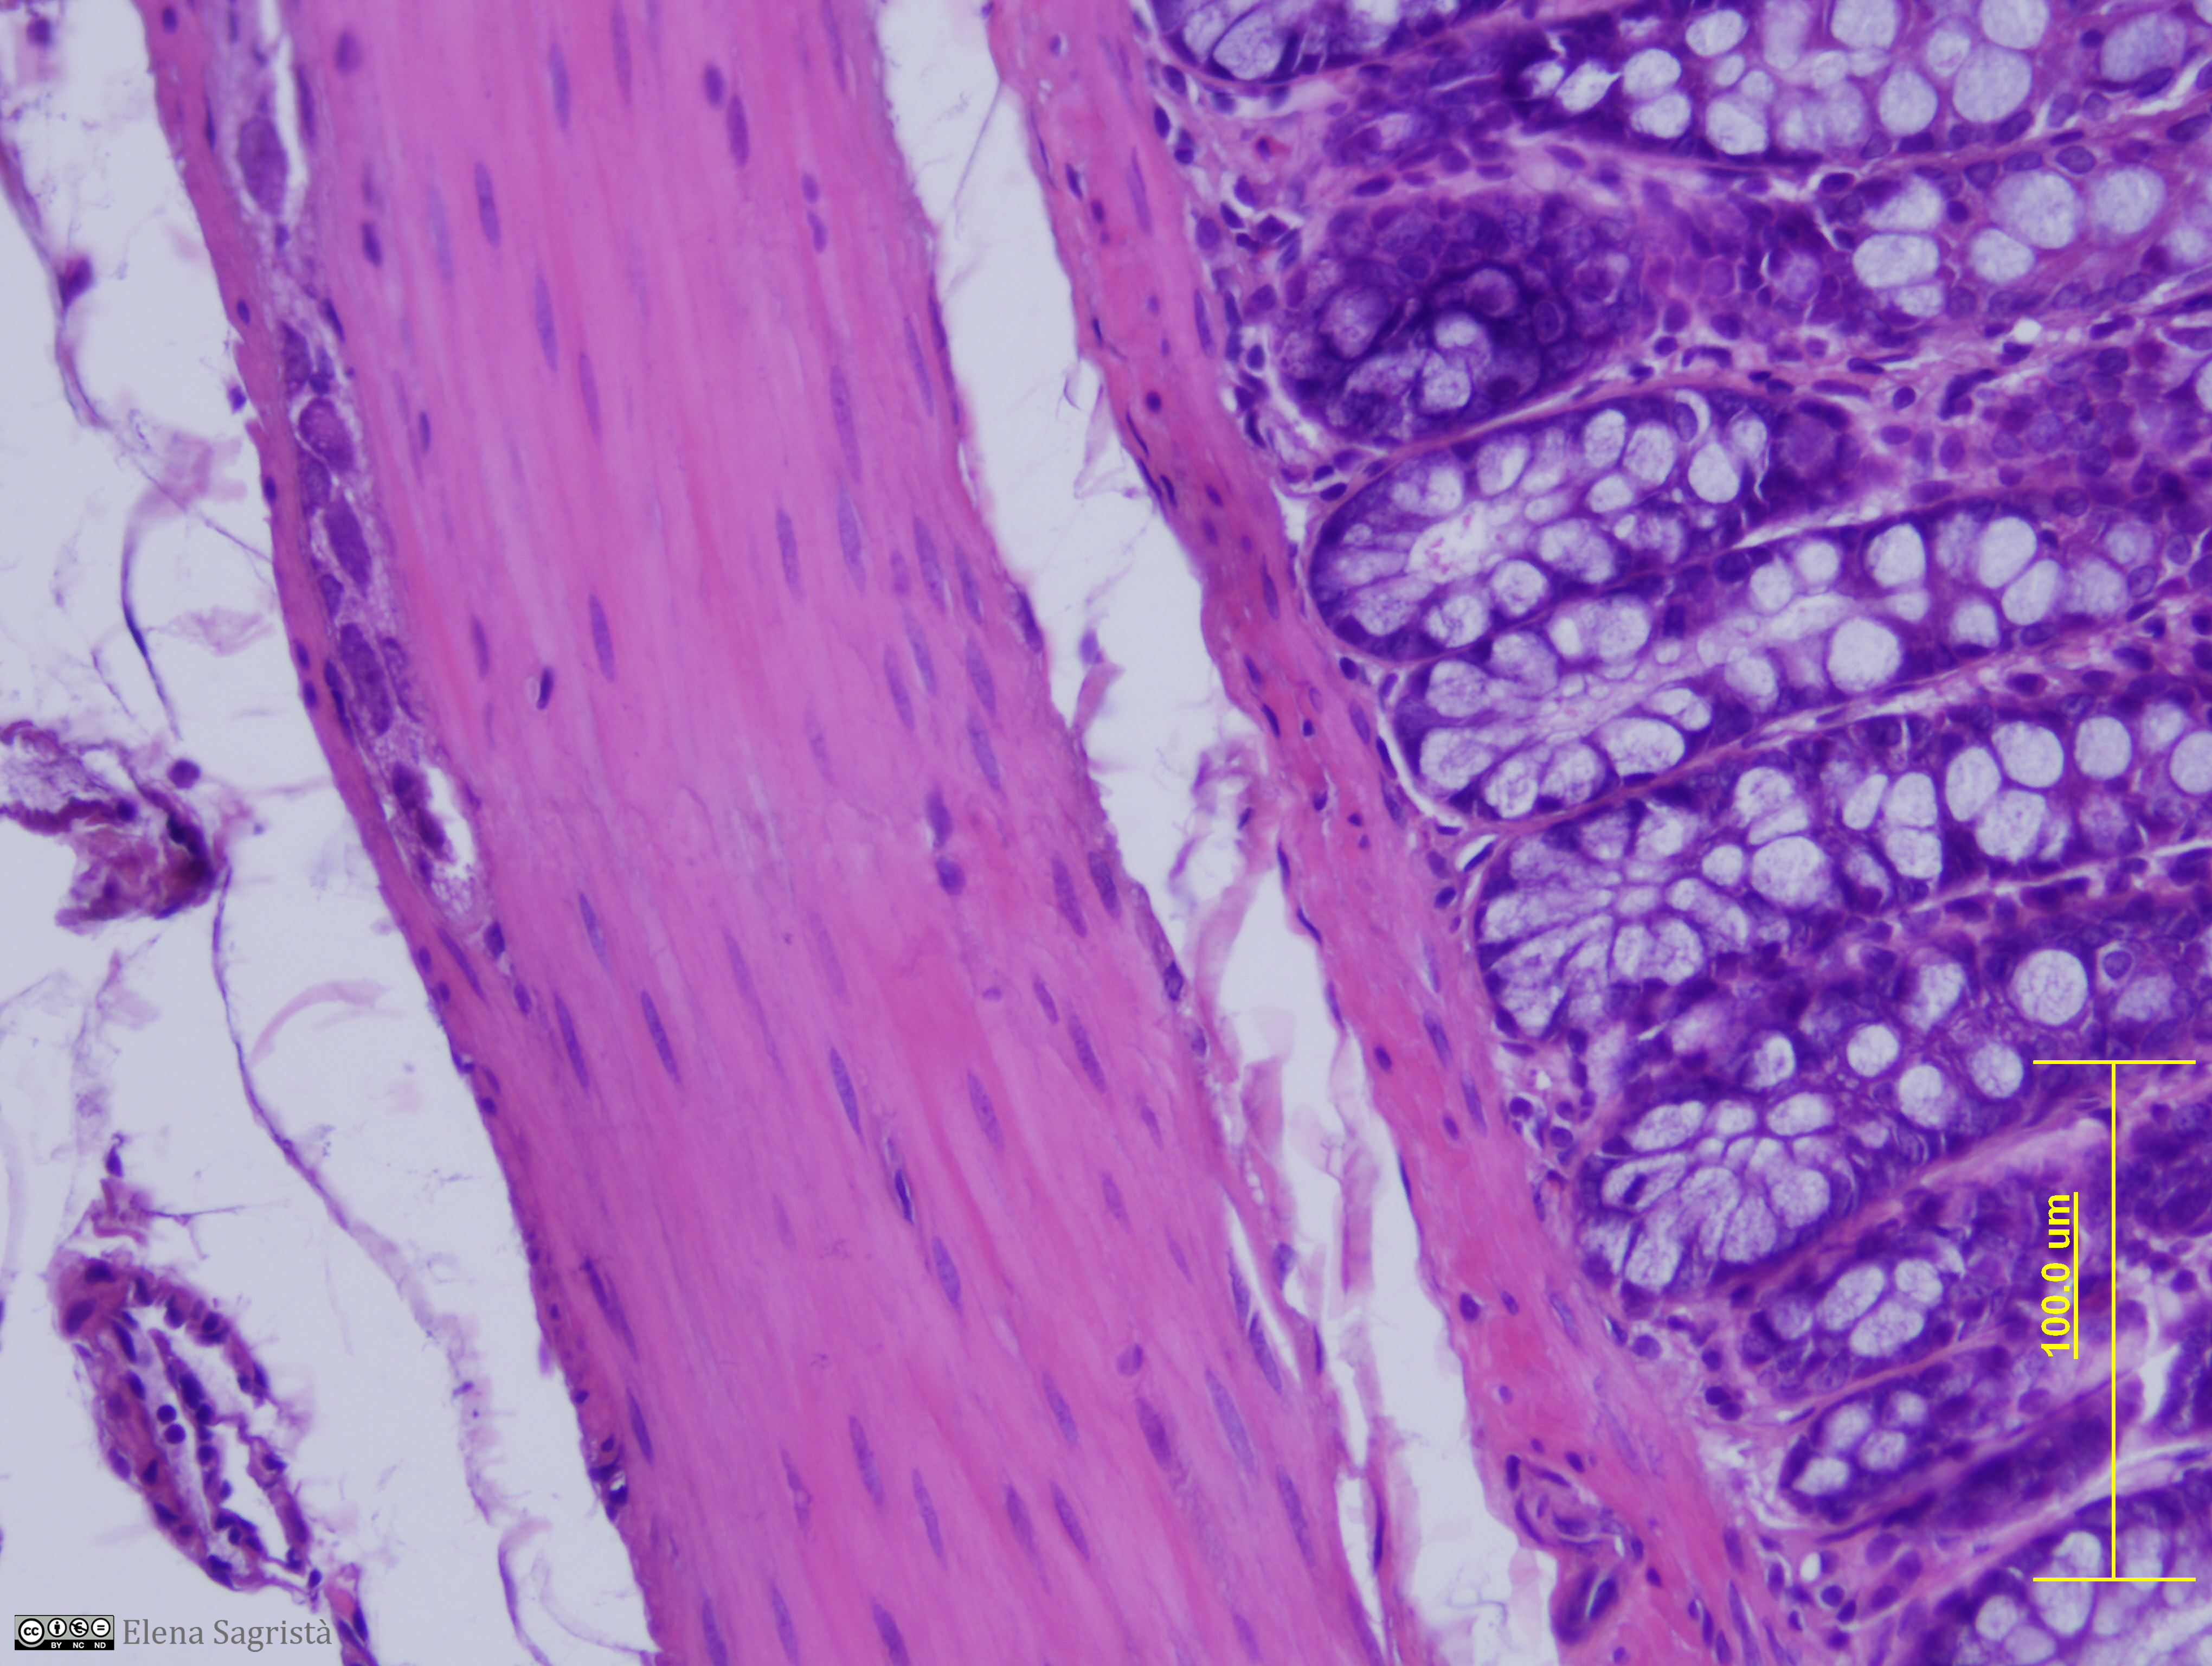

Histologia imatges: 07 Teixit muscular

Imatges de preparacions histològiques de Teixit muscular. Microscopia òptica.